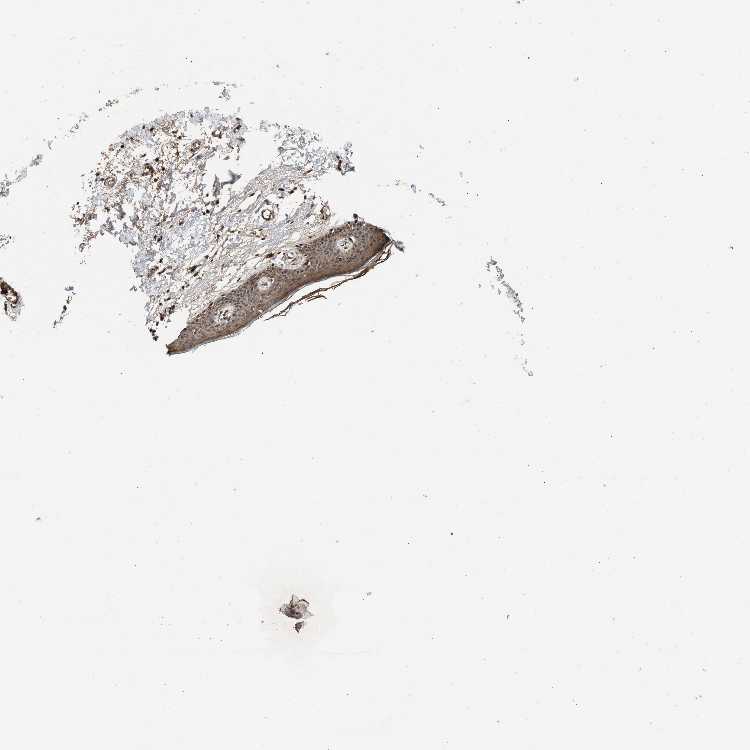

SKIN 2 - Antibody stainingi

Antibody staining in the annotated cell types in the current human tissue is reported as not detected, low, medium, or high, based on conventional immunohistochemistry profiling in selected tissues. This score is based on the combination of the staining intensity and fraction of stained cells.

Each image is clickable and will lead to virtual microscopy that enables deeper exploration of all samples and also displays staining intensity scores, fraction scores and subcellular localization as well as patient and tissue information for each sample.

Antibody HPA021297

Epidermal cells Medium